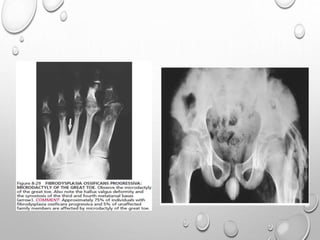

CONGENITAL DIGITAL ANOMALY

MICRODACTYLY OF IST TOE ..75% CASES , SOMETIME THUMB

( ABSENCE , SHORT PHALANX , SYNOSTOSIS)

HALLUX VALGUS

CLINODACTYLY

ECTOPIC OSSIFICATION

COLUMN OF BONES REPLACES LIGAMENTS , FASCIA , TENDONS

INTERVERTEBRAL DISC …HYPOPLASTIC , CALCIFIED

HYPOPLASTIC ANKYLOSED VERTEBRAL BODIES

(HYPOPLASIA DUE TO EARLY OSSIFICATIONOF SOFT TISSUE LEADS

TO PREMATURE FUSION OF CERVICAL GROWTH PLATE CENTERS)

BROAD FEMORAL NECK